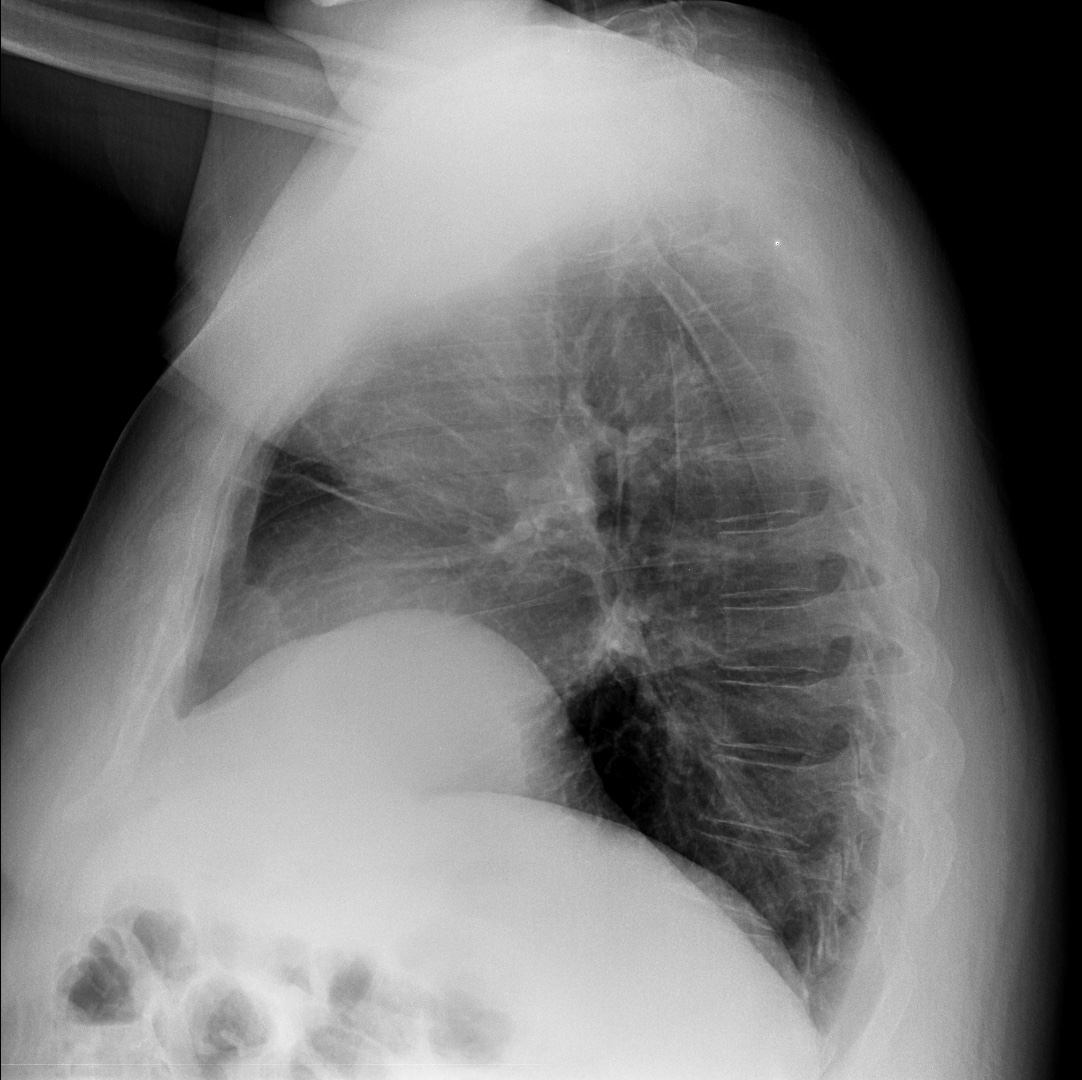

CASO: Febrícula y tos de 4 días de evolución.

Hallazgos:

- En la placa PA se observa una asimetría en los hilios pulmonares, el hilio izquierdo tiene una densidad aumentada.

- Tras examinar la placa lateral se observa un aumento de densidad en la columna que puede ser compatible con una condensación, es el signo de la desnificación vertebral.

SIGNO DE LA DENSIFICACIÓN VERTEBRAL: En la radiografía lateral normal, la densidad de la columna torácica tiende a disminuir desde la parte superior hasta el diafragma; la alteración de ese patrón por la presencia de una densidad superpuesta a la columna, indica la existencia de una consolidación pulmonar. Este signo adquiere especial valor cuando en la proyección posteroanterior la consolidación está oculta en el espacio retrocardíaco o en la base pulmonar.